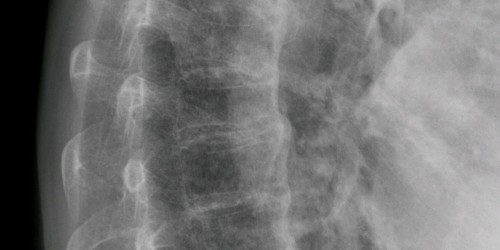

I have been dealing with weak knees for 5 months now...have had blood work, physical therapy for 5 months, seen an arthritic doctor, an EMG and waiting for my MRI of lower spine. I was told that my knees are not centered and I should have my tendons cut to center them. Other 2 doctors claim this was unecessary. I have been riding my bicycle for a month now religously, but still have knee problems off and on. Does anyone have any ideas? My knees just feel weak...no joint pain nor any knees giving out.